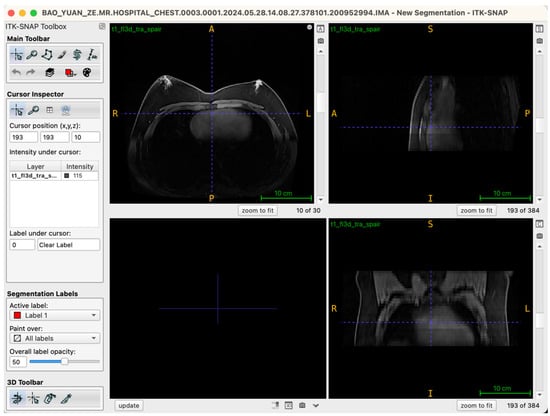

The procedural workflow is as follows: after the seed points are placed and labels assigned, the operator enters the “Segment 3D” module and activates the “Run Snake” function. The software then assesses local image intensity in proximity to seed points, executing localized contour evolution. The segmentation process is visualized in real time within a 3D preview window, where the operator can observe contour convergence, boundary accuracy, and structural fidelity relative to the intended tissue morphology. Importantly, the Snake algorithm is executed independently for glandular (Label 1) and adipose (Label 2) tissues, ensuring mutual exclusivity and clarity of boundaries (Figure 4).

Figure 4.

Workstation schematic of glandular tissue segmentation evolution.

Following model generation, ITK-SNAP’s synchronized multi-planar viewing functionality is used for comprehensive quality review. Segmentation boundaries are inspected, slice-by-slice, in axial, sagittal, and coronal planes to confirm precise anatomical adherence and to identify any instances of over-segmentation (“false positives”) or under-segmentation (“missed tissue”). If incomplete contours, boundary drift, or spurious segmentations are detected, the operator can iteratively adjust seed-point distribution and rerun the Snake segmentation until continuous, well-conformed, and topologically accurate models are achieved.